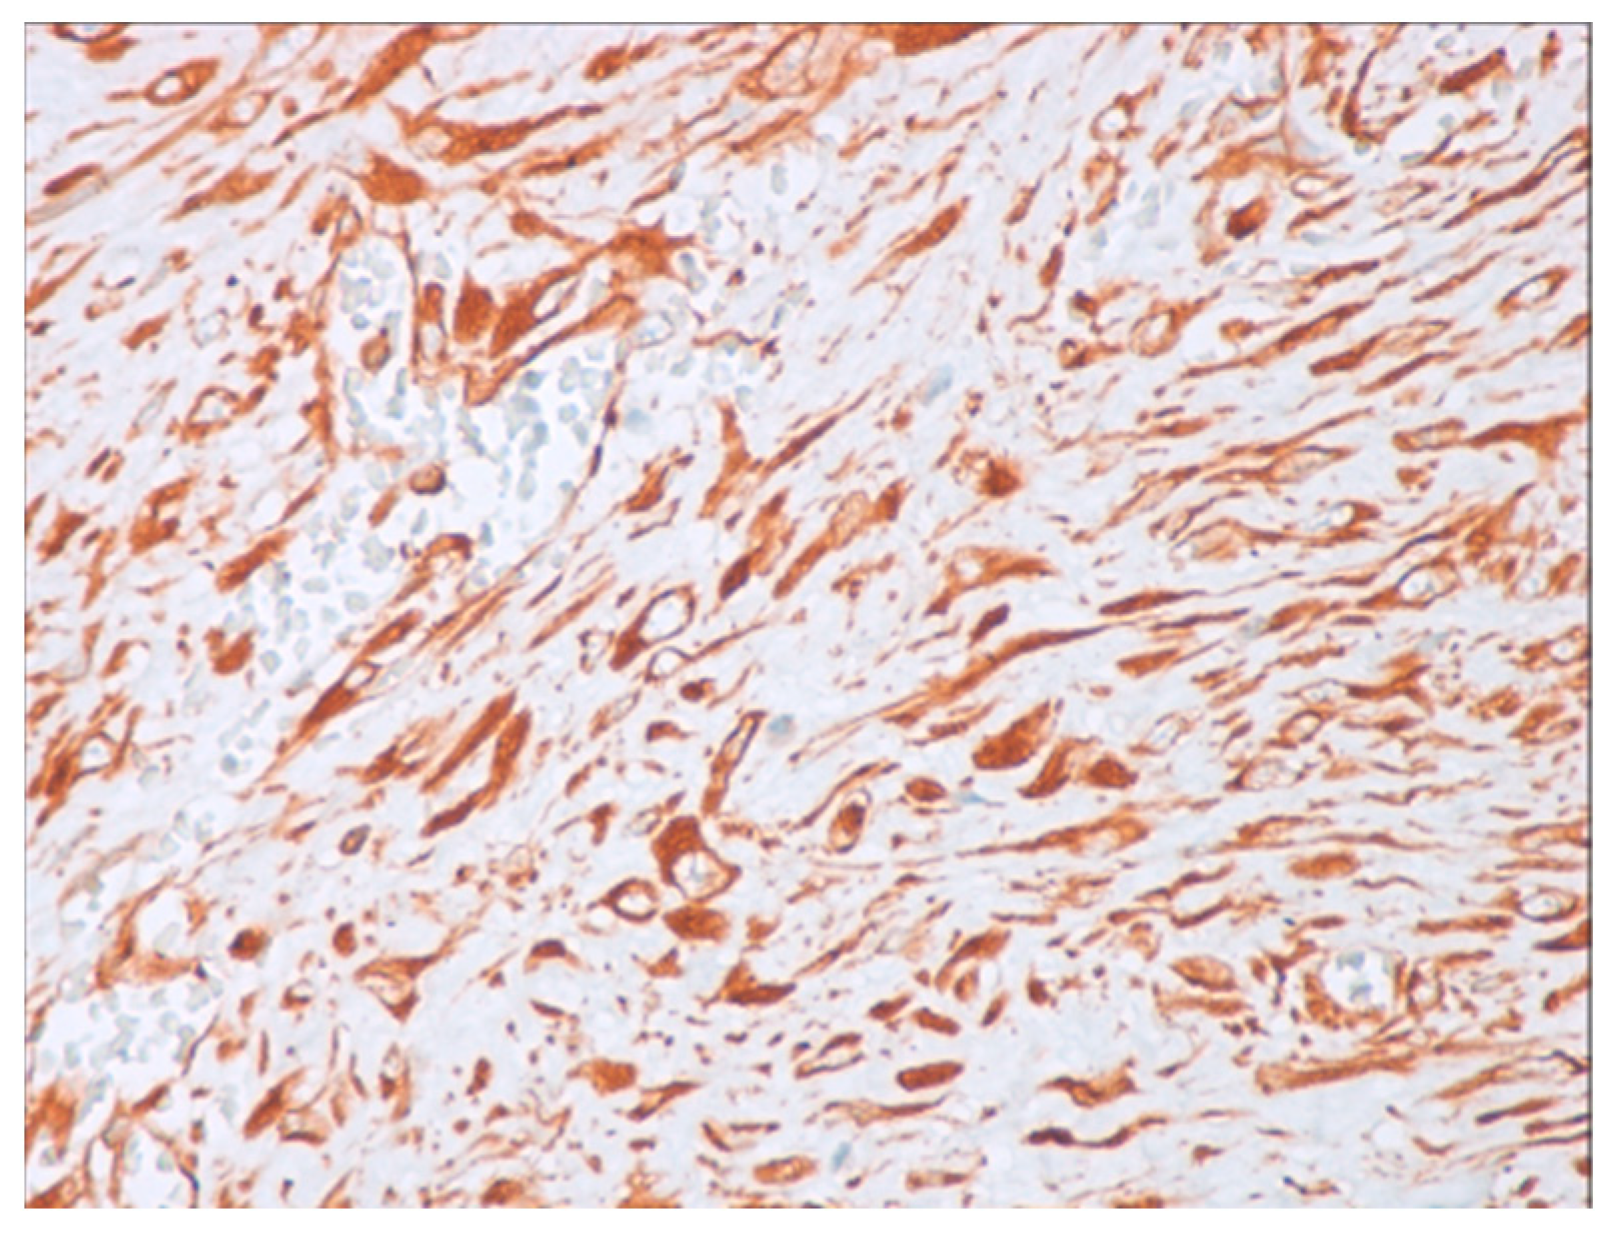

4.3. Histopathological Diagnosis

4.4. Pathology